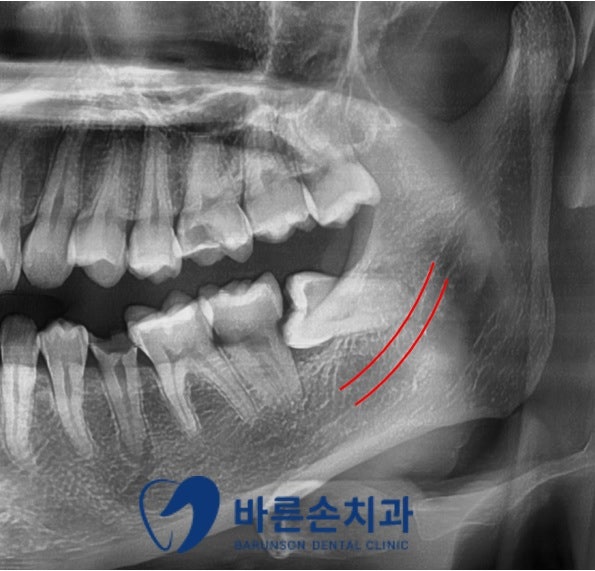

저희 치과에 내원해 주신 환자분의 사진입니다

환자분께서는 아래 사랑니가 옆으로 누워서 난 매복 사랑니 상태이며

그로 인해 관리가 어렵고 음식물이 끼어

충치와 치주 질환이 발생하여 불편감을 호소한 케이스입니다

발치전 파노라마와 3D-CT 촬영을 통해

사랑니의 형태와 위치 및

아래턱뼈 하치조신경관의 해부학적 위치를 정확히 확인 후

발치를 진행하게 됩니다